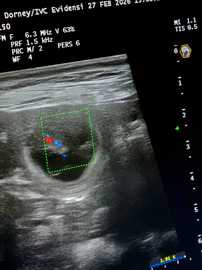

4. Woche     26.Trächtigkeitstag

Heute waren wir zum Ultraschall und was soll ich sagen:

Lani`s Bauch ist voller kleiner Blubberbläschen.

Wir konnten auch schon die kleinen Herzchen schlagen sehen und alles ist für die Zeit bestens entwickelt.